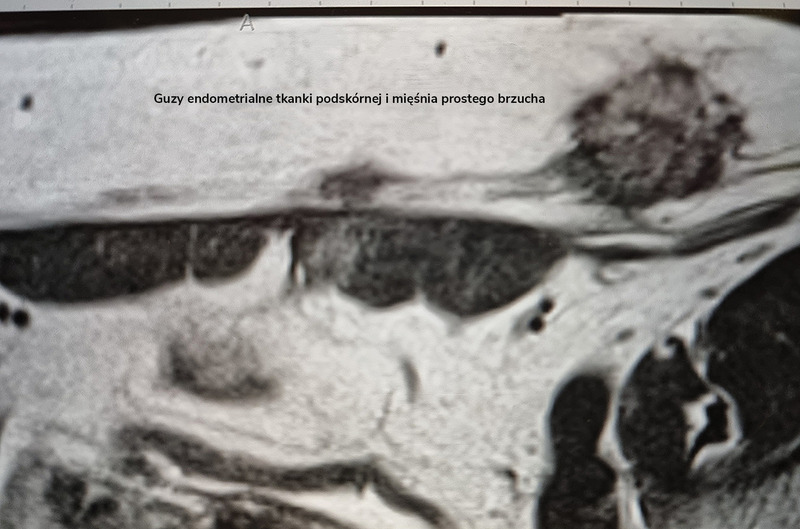

Alternatywnym badaniem, które umożliwia obiektywne i trwałe zobrazowanie zmian powłok brzucha, jest MR. Niemniej ze względu na znacznie wyższy koszt tego badania i długi czas oczekiwania na opis wykorzystywane jest ono raczej w sytuacjach trudnych diagnostycznie: u pacjentek otyłych, po przebytych licznych operacjach zmieniających architektonikę powłok brzucha, w diagnostyce zmian bardzo rozległych z podejrzeniem o naciekanie oraz – paradoksalnie – zmian bardzo drobnych, niewidocznych wyraźnie w USG, a przede wszystkim w przypadku guzów o nietypowej morfologii, wybitnym unaczynieniu lub szybko wzrastających, czyli podejrzanych onkologicznie.

Badanie MR w kierunku obecności endometriozy, w tym także AWE, wymaga oceny przez doświadczonego radiologa, ponieważ w przesiewowym, rutynowo wykonywanym skanie, z założenia skupionym na opisie narządów miednicy mniejszej lub jamy brzusznej, zmiany nie są zazwyczaj opisywane, co daje pacjentkom, a często również ich lekarzom, błędne przeświadczenie, że w danym miejscu nie ma zmian patologicznych (ryc. 3).